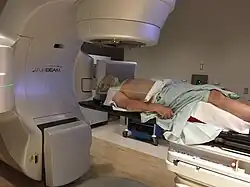

| Treatment | Surgery, radiation, chemotherapy |

Radiotherapy

Concerns over the morbidity associated with traditional open surgical en-bloc resection led to exploring alternative approaches using radiation.[122] Intensity-modulated radiation therapy (IMRT) can provide good control of primary tumours while preserving excellent control rates, with reduced toxicity to salivary and pharyngeal structures relative to earlier technology. HPV+OPC has shown increased sensitivity to radiation with more rapid regression, compared to HPV-OPC.[133] Generally, radiation can safely be delivered to the involved side alone (ipsilateral), due to the low rate of recurrent cancer on the opposite side (contralateral), and significantly less toxicity compared to bilateral treatment.[e][135][134] IMRT has a two-year disease-free survival between 82 and 90%, and a two-year disease-specific survival up to 97% for stage I and II.[136][137]

Reported toxicities include dry mouth (xerostomia) from salivary gland damage, 18% (grade 2);[f] difficulty swallowing (dysphagia) from damage to the constrictor muscles, larynx and oesophageal sphincter, 15% (grade 2); subclinical aspiration up to 50% (reported incidence of aspiration pneumonia approximately 14%); hypothyroidism 28–38% at three years (may be up to 55% depending on amount of the thyroid gland exposed to over 45 Gy radiation; esophageal stenosis 5%; osteonecrosis of the mandible 2.5%; and need for a gastrostomy tube to be placed at some point during or up to one year after treatment 4% (up to 16% with longer follow up).[12][139][137][140][141] Concerns have been expressed regarding excessive short- and long-term toxicity, especially dysphagia, and xerostomia,[142][143][144] and hence whether standard doses expose patients with better prognoses are being exposed to overtreatment and unnecessary side effects.[145][91]